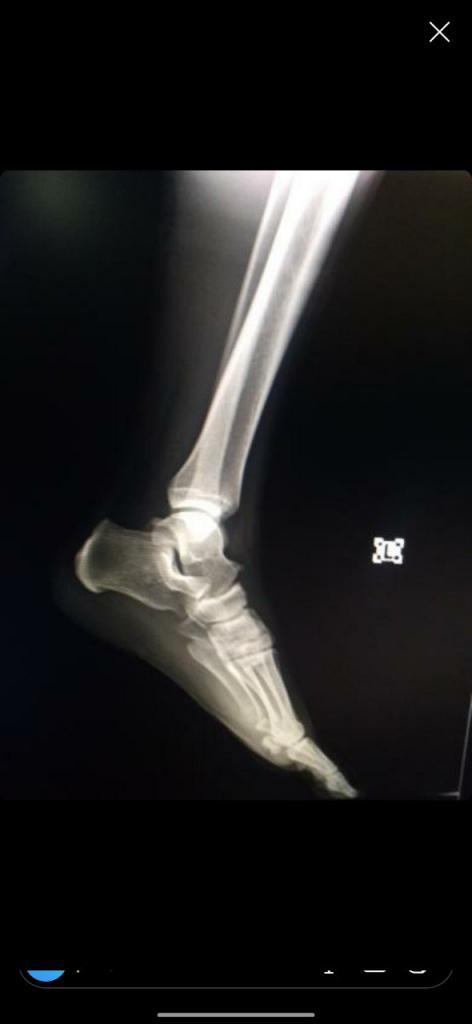

Нажмите на изображение для увеличения

Название: IMG_20200204_214003_668.jpg

Просмотров: 26

Размер:	20.8 Кб

ID:	13293269Нажмите на изображение для увеличения

Название: IMG_20200204_214000_006.jpg

Просмотров: 29

Размер:	21.2 Кб

ID:	13293270Дорогие врачи! Как по вашему, тут есть трещина?

Заранее спасибо!

Цитата Сообщение от Люси Посмотреть сообщение

Вложение 13293269Вложение 13293270Дорогие врачи! Как по вашему, тут есть трещина?

Нужны более качественные снимки. Сами снимки, может, и ничего, а вот их фото, плохого качества и маленькое. Мы ищем мельчайшие детали, а тут все маленькое и как в тумане)) По этим снимкам трещины не вижу, но и исключить не могу. Если есть в электронном виде, то выложите их.